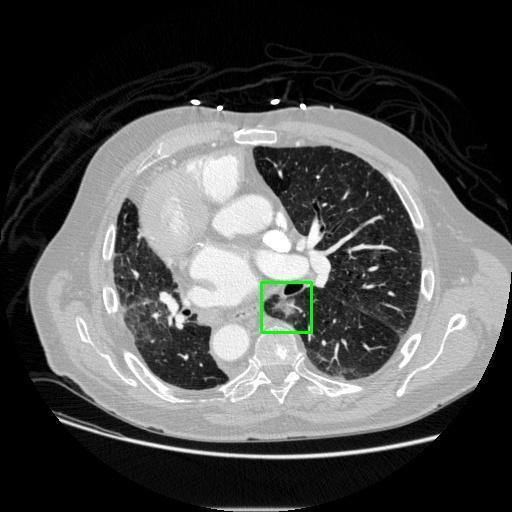

We developed an AI-based system using deep learning models for analyzing lung CT scans to detect and classify pulmonary nodules. We chose the YOLOv11 architecture for its enhanced object detection capability and adapted it specifically for medical imaging, incorporating pixel-level precision and severity classification.

Classification into three severity levels with colored bounding boxes.

Successfully built and deployed an AI model (YOLOv11) capable of detecting lung nodules in CT scans with high accuracy and real-time performance.

Designed a severity classification system that categorizes nodules into null, moderate, and severe using colored bounding boxes, assisting in rapid clinical decision-making.